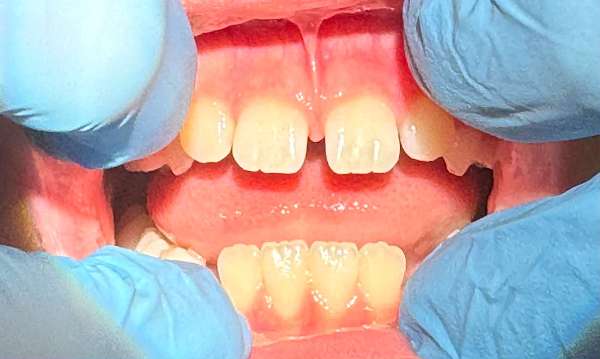

Frenectomy/Lip Release

CO2 Laser using to perform a frenectomy or lip release. The use of CO2 laser allows for treatment to completed very quickly with minimal tissue bleeding. Gingival tissues heal beautifully after laser treatment.